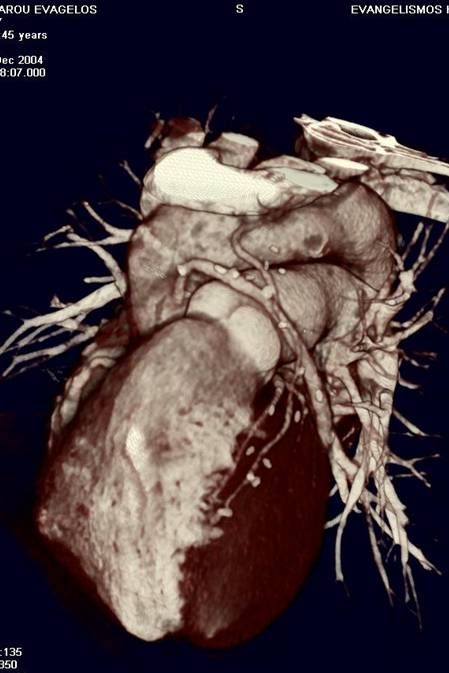

The non-invasive imaging modality of multi-detector computed tomography has dramatically evolved the last ten years and that is due to hardware and software developments. The newer generation of scanners allows increased spatial and temporal resolution that improves the clinical reliability giving further insights into the evaluation of coronary artery disease. Heart morphology imaging followed by studies of myocardial function and assessment of cardiac valves can be performed from the information derived from the data of the coronary artery examination. Also, the venous anatomy of the heart, coronary artery bypass grafts, stents, and cardiac tumors can be imaged and evaluated when necessary. For the beneficial use of this method, entrance criteria for different patient groups need to be set in order to allow improved outcome of multi-detector CT.